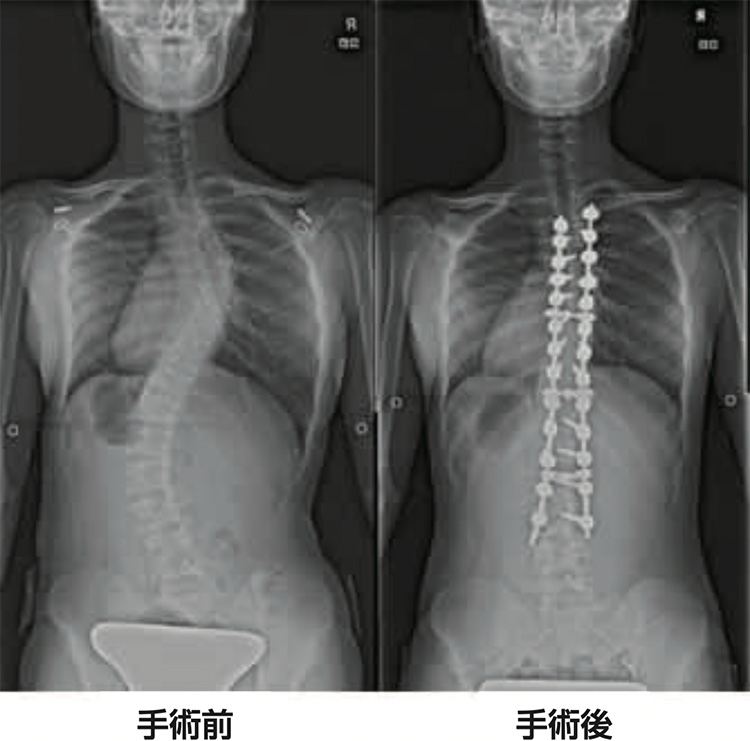

小児脊柱変形治療に関する最新の知見を提供する専門書。- タイトル: 小児脊柱変形治療の最前線- 著者: 川上恵明, 学野晴行- 出版社: 南江堂- 言語: 日本語- 学会: 日本脊椎矯正学会購入しましたが、必要なくなり、読んではおらず開いていない状態です。購入当初からだったと思いますが、カバーに多少のスレと引っかき傷があります。(3枚目写真)